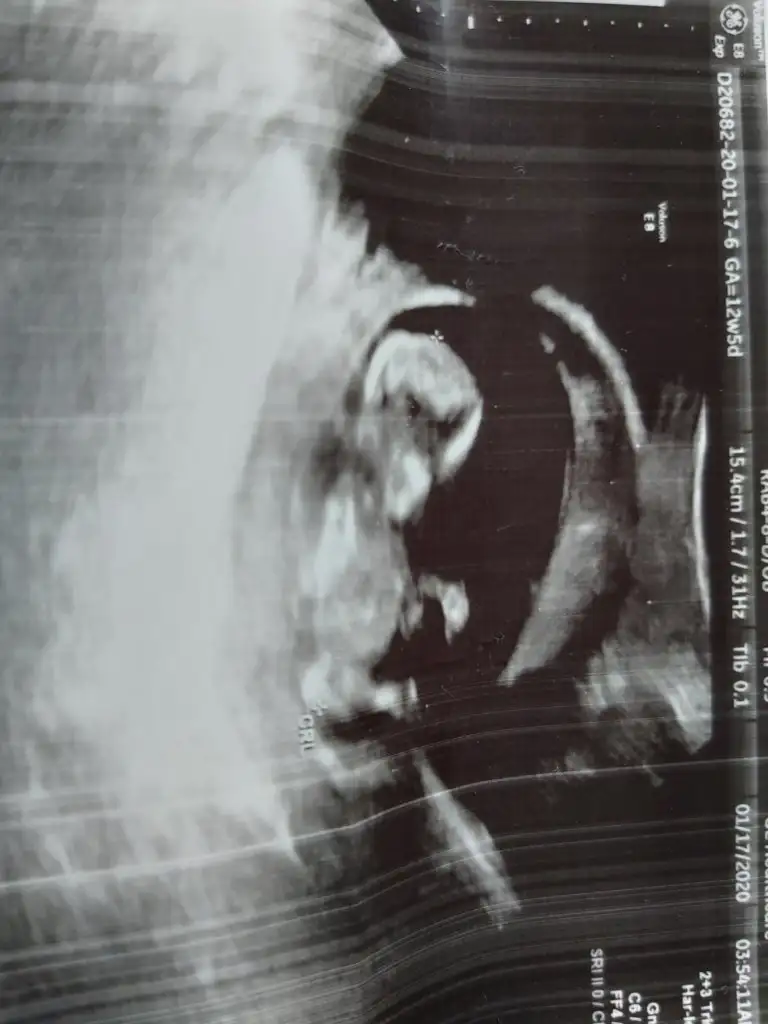

dr soylemeden siz gorun genital nub teorisi ( bebegin cinsiyeti)

Haftam yaklaştıkça bir merak sardı.

O gözüken nub mu emin olamadım ama yine de bir atayım belki fikir yürüten olur didimm.

10+5 günlük bir kurbağa 🐸 🐣

Ne dersiniz?? Ikra meyra Ikra meyra